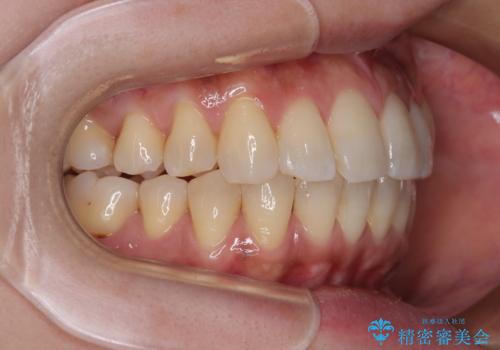

インビザラインによる矯正治療と奥歯のインプラント治療

- 全体的なデコボコと、以前抜歯した歯のスペースを閉じた部分が気になるとのことで来院された患者様です。

左上第一大臼歯を抜歯した際に、スペースを閉じたそうですが、歯が傾斜してものが挟まって不快とのことでした。

インビザライン矯正で全体の歯列と整えるとともに、左上第一大臼歯部にはスペースを作り、インプラントによる補綴治療を行うこととしました。

歯の傾斜が改善され、インプラントによるクラウンが装着されたことで、物が挟まることもなくなりました。